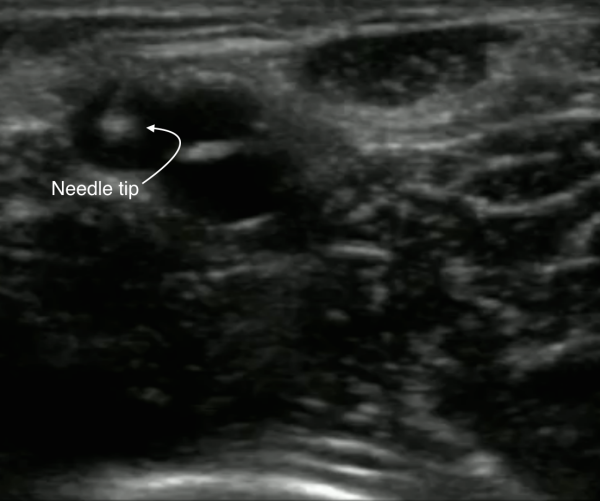

8. Pierce the vein looking for the “target sign” or “bull’s eye sign” (the hyperechoic needle tip in the center of the anechoic vessel)— you should see a corresponding flash of blood in the catheter once the needle tip has pierced the vessel.

Image 4. Hyperechoic needle tip localized in a blood vessel in short axis. This is called the “target sign” or “bull’s eye sign.” Image Courtesy of Sierra Beck, MD and Bradley Wallace, MD.